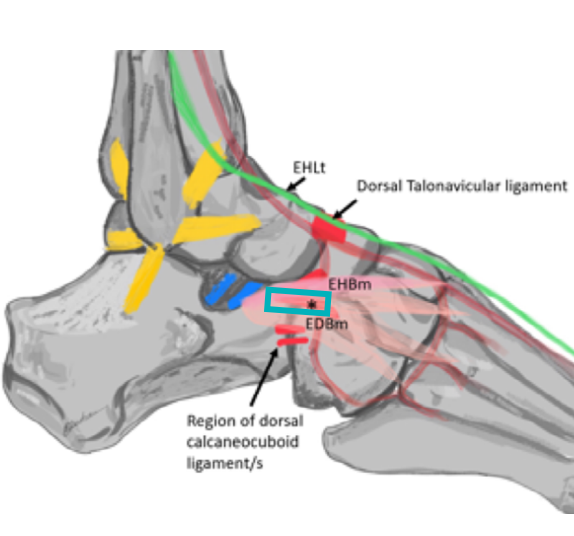

@ DOI: 10.1002/sono.12300

이분인대(Bifurcate ligament)

이분인대는 종골에서 두갈래로 갈라지는 인대입니다.

1) 종입방인대(Calcaneo-cuboid ligament)

: 종골과 입방골(cuboid)에 연결

2) 종주인대(Calcaneo-navicular ligament)

: 종골과 주상골(navicular)에 연결

Y자 혹은 V자로 갈라져

발등뼈의 안정성을 높이고

발의 아치를 유지하는 역할을 합니다.

좌측 모식도 @ DOI: 10.1002/sono.12300 / 우측 초음파 영상은 직접 스캔했습니다

민트색 박스로 표시한 부위에

프로브를 댄 영상입니다.